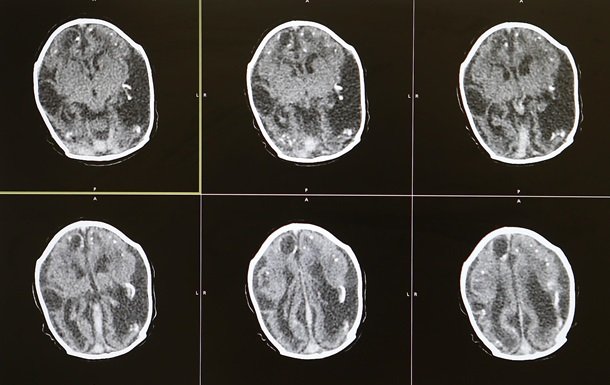

Японські вчені виявили, що в мозолистому тілі пацієнтів зі шизофренією знижена концентрація одного з основних елементів ліпідного обміну головного мозку.

Інша відома ознака шизофренії - порушення структури білої речовини і її нестача в головному мозку, але про біологічну основу такої зміни відомо досить мало.

За допомогою мас-спектрометрії вчені оцінили концентрацію сфінголіпідів у мозолистому тілі (найбільшому скупченні білої речовини головного мозку) й одній із ділянок кори - премоторній зоні.

Аналіз проходив post mortem: вчені зібрали зразки мозку 15 пацієнтів із шизофренією, 15 пацієнтів з біполярним розладом, 15 - із депресією і 15 здорових людей.

Аналіз показав, що в мозолистому тілі пацієнтів із шизофренією, на відміну від контрольної групи, на 31 відсоток нижча концентрація сигнального сфінголіпіда сфінгозин-1-фосфату. Його концентрація в мозку інших пацієнтів - з депресією і біполярним розладом - істотно не відрізнялася від контрольної групи.